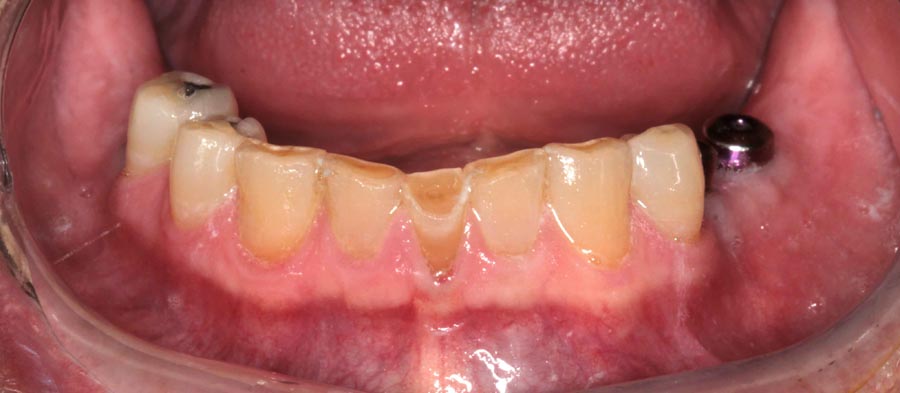

Three months later the patient returns for a series of appointments to fabricate his final prostheses. This is when we note that his homecare is slipping. Notice the redness at the gums that wasn’t seen previously. He was alerted to the issue and educated on how to improve.